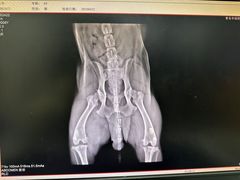

• 小叮当动物医院·骨科·眼科

• -小叮当动物医院·骨科·眼科

超喜爱的大果子 | 24-01-01